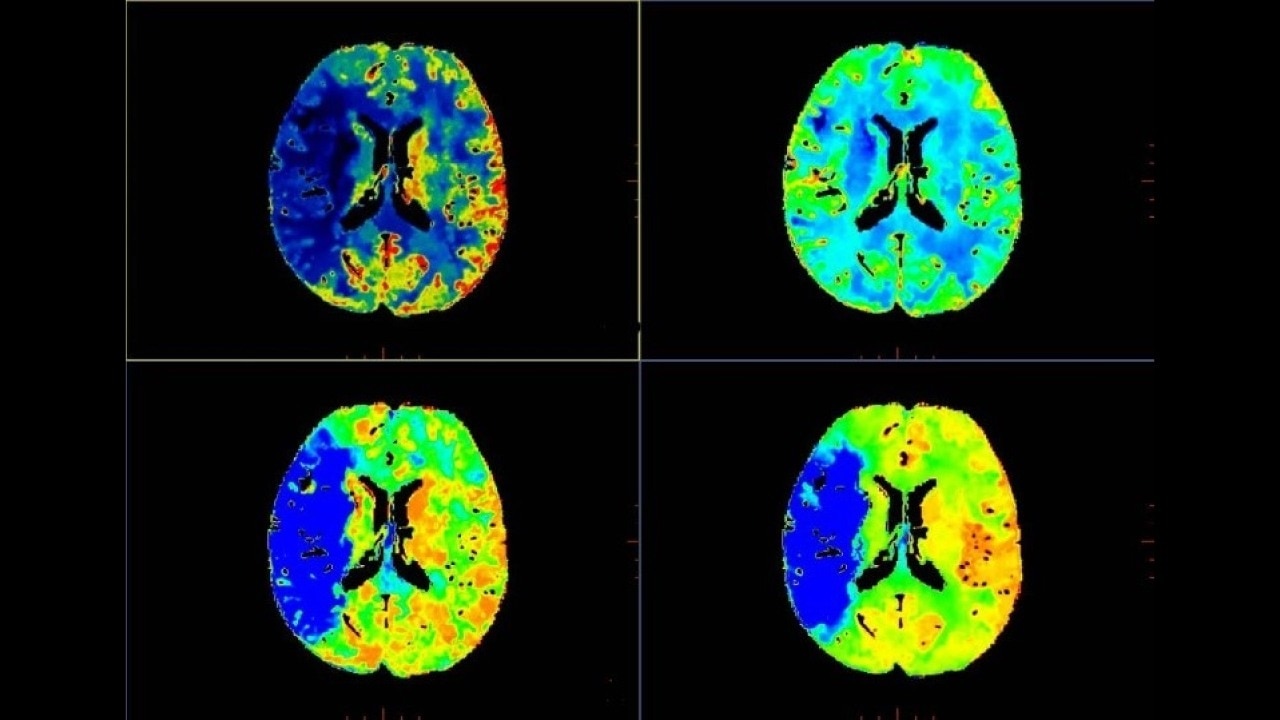

CT Perfusion 4D

Fast, easy-to-use automated software for analyzing CT Perfusion images related to stroke, tumor angiogenesis and dynamic myocardial perfusion.

Brain perfusion

Easy-to-use automated workflow for CT stroke and tumor angiogenesis evaluation

Brain stroke protocol

• Image Registration to minimize the effects of patient movement

• Bone Removal to remove the cranium automatically from the dataset

• Deep Learning brain ventricle segmentation to prevent ventricular matter inclusion in quantitative results and improve visual inspection of the maps

• Automated selection of arterial input and venous output. Both can be easily adjusted if needed.

• Automated generation of all functional maps: Blood Flow, Blood Volume, Mean Transit Time, and Transit Time to IRF Peak (Tmax)

• Automatically define the symmetry plane to be used for mirroring ROIs and relative thresholds

• Tissue Classification enables the visualization of regions that are segmented from absolute or relative values, customizable thresholds and user selectable input maps

• Mismatch volume and ratio are calculated from the modified perfusion volume and low perfusion volume ROIs